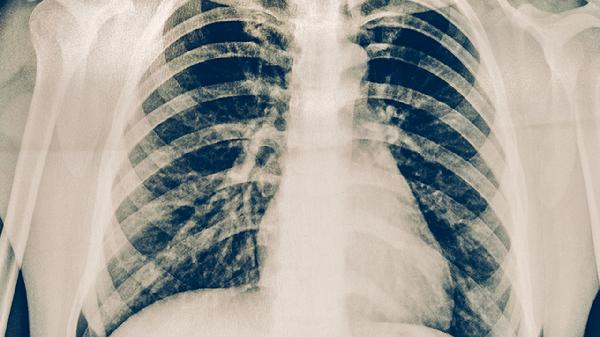

活动性肺结核患者是主要传染源,应减少与咳嗽、咳痰症状明显者的密切接触。在医疗机构或结核病高发区域需规范佩戴口罩,保持1米以上社交距离。若家庭成员确诊肺结核,其他成员应进行结核菌素试验和胸部影像学筛查。

高危人群应每年进行胸部X线检查,出现持续两周以上咳嗽、低热、盗汗等症状时需及时就医。糖尿病患者、HIV感染者等免疫力低下者,可遵医嘱预防性使用异烟肼片。密切接触者需完成6-9个月的医学观察。